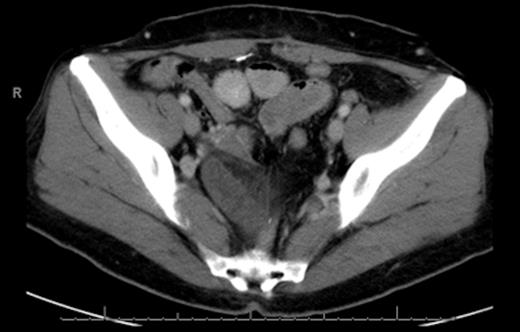

The initial management consisted of a NG tube insertion, IV hydration, and serial abdominal exams. Later, the patient was taken to the operating room due to the significant worsening of her pain. The abdomen was insufflated via the umbilicus with a Veress needle and a 5mm port was placed. Extensive adhesions were visualized throughout the pelvis which was carefully divided. The majority of the small bowel was normal in appearance (Fig. 3), but a segment of 1.5 feet was ischemic and surrounded by dense adhesions (Fig. 4).